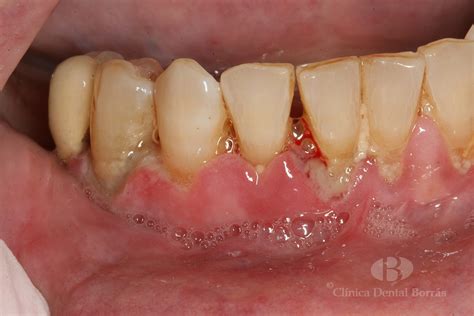

Los síntomas de la gingivitis necrotizante son generalmente severos y se presentan de manera aguda. Adopta la forma de una infección aguda y dolorosa por la que sangran las encías, con necrosis de las papilas gustativas y deterioro de la salud bucal. El manual de MSD informa de que la infección suele comenzar de forma repentina, con dolor y sangrado de las encías, así como con una salivación excesiva. Debido a todos estos síntomas, el paciente tendrá dificultades para realizar actividades comunes como hablar, comer y tragar.

- Úlceras y llagas en las encías.

- Tejido necrosado.

El diagnóstico de la gingivitis necrotizante se basa en el examen clínico realizado por un dentista o periodoncista. Normalmente, resulta posible detectar la gingivitis necrosante a partir del aspecto de la boca y las encías. La evaluación incluye la inspección visual de las encías para identificar signos de necrosis, úlceras y sangrado. Afortunadamente, muchos problemas en las encías pueden ser percibidos a primera vista por un dentista experimentado.